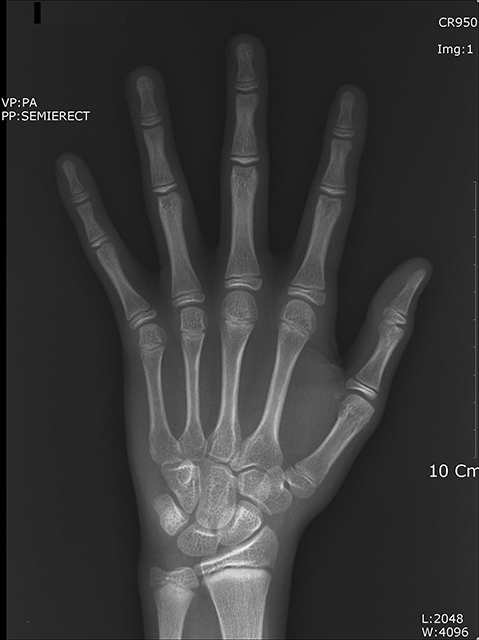

¾Æ·¡ÅÎÀÌ ÈÄÅðµÈ II±Þ ºÎÁ¤±³ÇÕÀÇ °æ¿ì Èıâ È¥ÇÕÄ¡¿±â¿¡ Ä¡·áÇÏ´Â °ÍÀÌ ÁÁÀ¸¸ç Ä¡·É(dental age)»Ó¸¸ ¾Æ´Ï¶ó ¼ºÀåÆÇ °Ë»ç¿¡ ÀÇÇÑ °ñ·É(skeletal age), ¼ºÀû¡ÈÄ µîÀ» Âü°íÇÏ´Â °ÍÀÌ ¹Ù¶÷Á÷ÇÕ´Ï´Ù(±×¸²3). À̴ Ű°¡ ¸¹ÀÌ ÀÚ¶ö ¶§ ÅÎÀÇ ¼ºÀåµµ Ȱ¹ßÇØ Ä¡·áÈ¿°ú°¡ ÁÁ±â ¶§¹®ÀÔ´Ï´Ù. ÇÏÁö¸¸ ½ÉÇÑ °ñ°Ý¼º ¹®Á¦°¡ ÀÖ´Â °æ¿ì È¥ÇÕÄ¡¿±â Ãʱ⿡ Ä¡·á¸¦ ½ÃÀÛÇϱ⵵ ÇÕ´Ï´Ù.